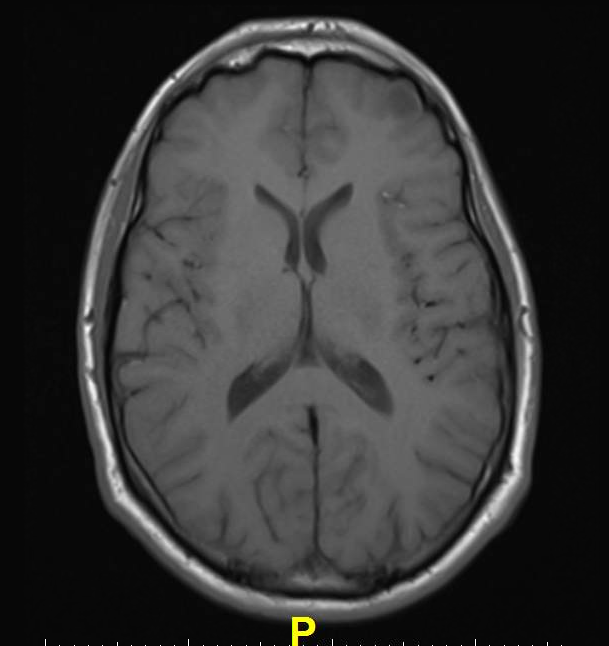

However, in recent years, clinicians in Japan noticed that patients with a history of multiple administrations of Gd-CM showed areas of high intensity, or hyperintensity, on MRI in two brain regions: the dentate nucleus (DN) and globus pallidus (GP). The precise clinical ramifications of hyperintensity are not known, but hyperintensity in the DN has been associated with multiple sclerosis, while hyperintensity of the GP is linked with hepatic dysfunction and several diseases.

To learn more, the researchers compared unenhanced T1-weighted MR images (T1WI) of 19 patients who had undergone six or more contrast-enhanced brain scans with 16 patients who had received six or fewer unenhanced scans. The hyperintensity of both the DN and the GP correlated with the number of Gd-CM administrations.

“The hyperintensity of DN and GP on unenhanced T1WI may be due to gadolinium deposition in the brain independent of renal function, and the deposition may remain in the brain for a long time,” Kanda suggested.